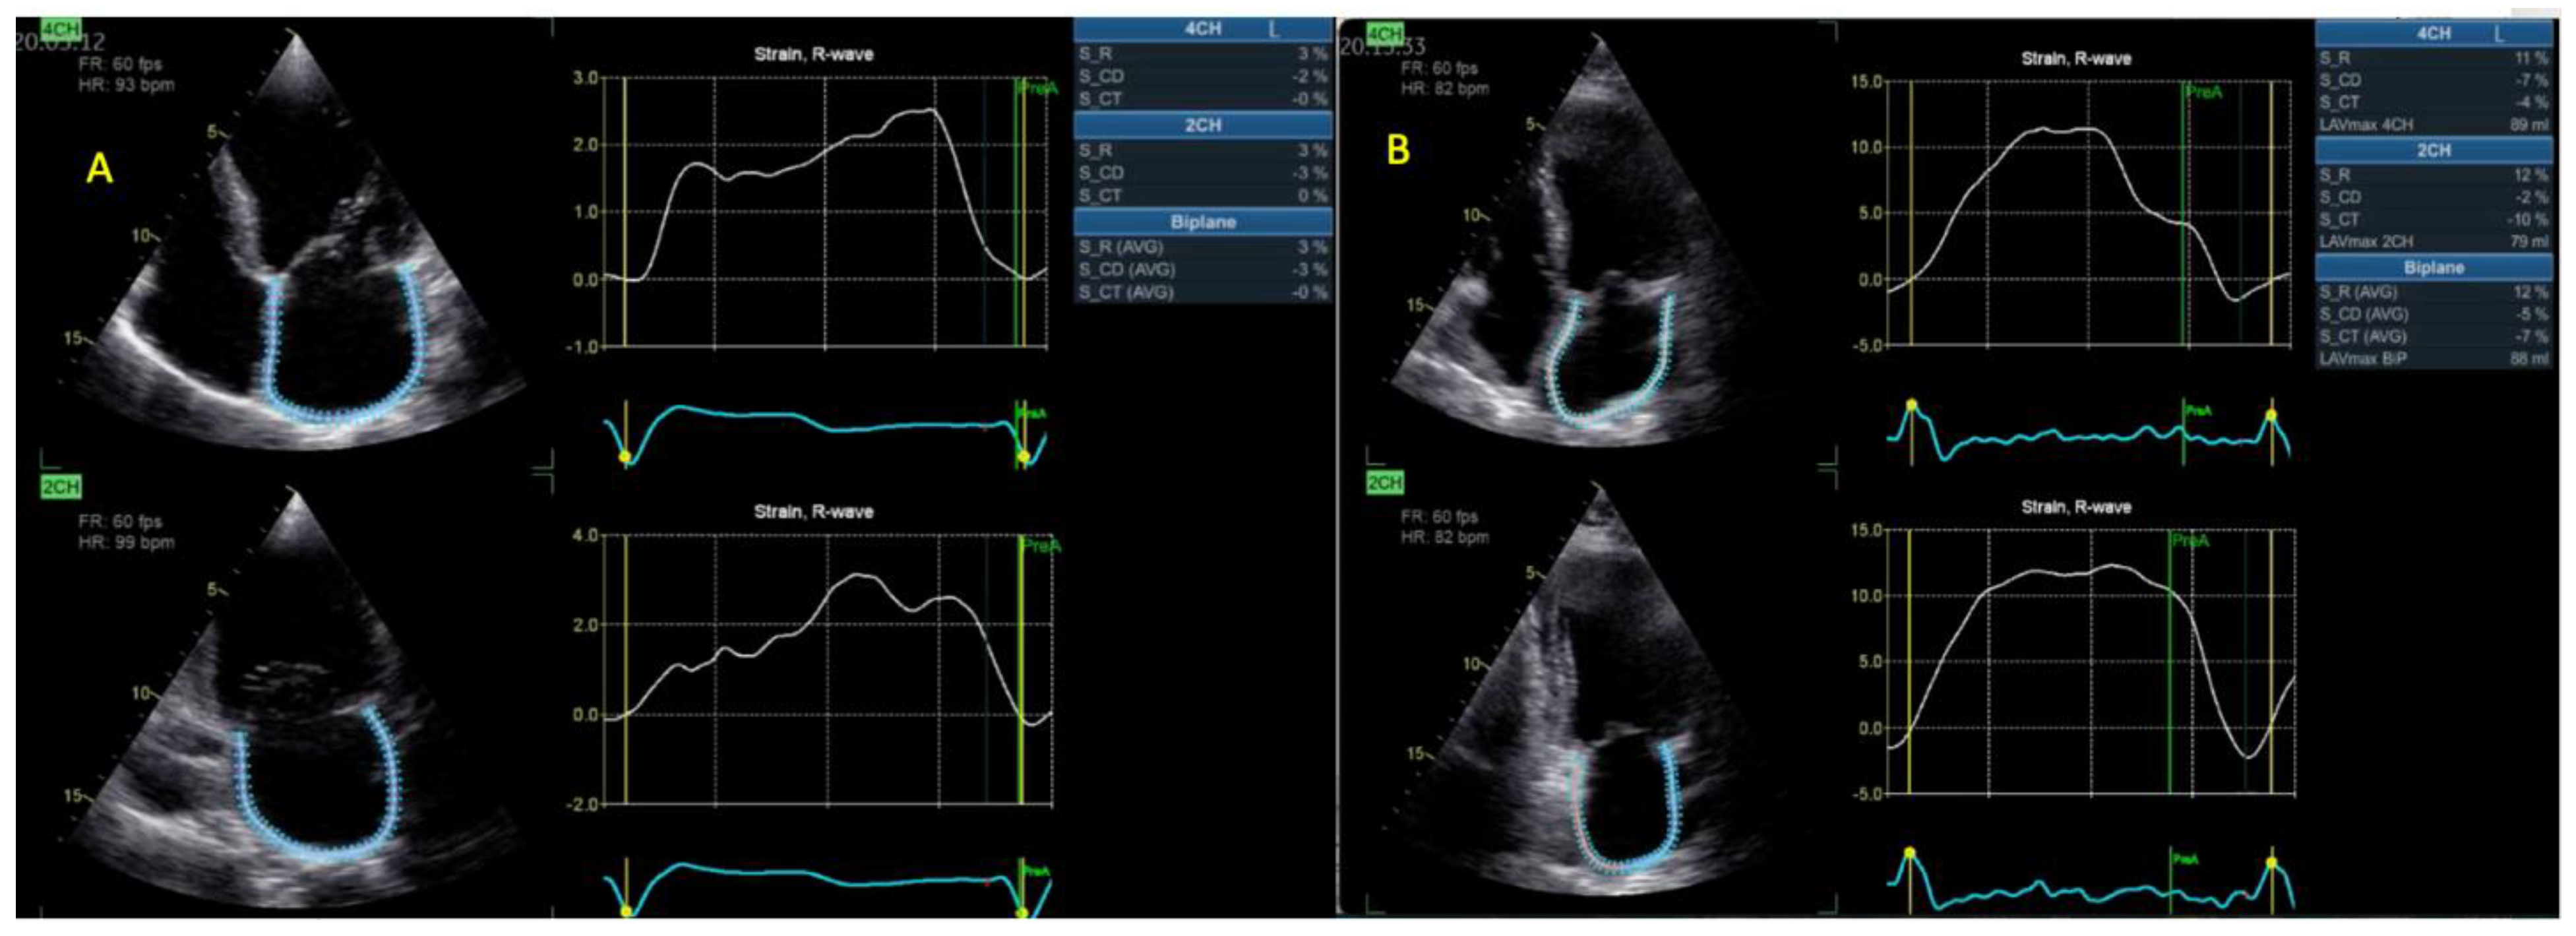

| BP LASr (%) | 12.3 ± 7 | 6.9 ± 3 | <0.001 |

| RASr (%) | 22 ± 12 | 9 ± 6 | <0.001 |